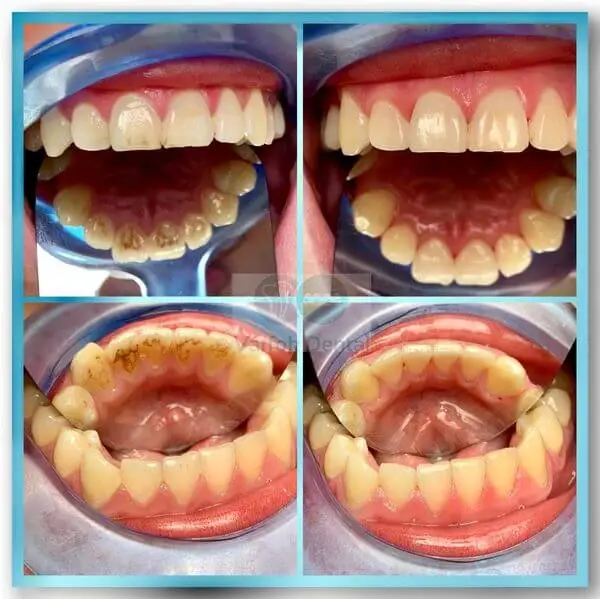

Fogkő eltávolítás

Fogaink egészségének megőrzése érdekében nagyon fontos a rendszeres fogkő eltávolítás beiktatása.

A rendszeres dentálhigiéniai kezelés segít a súlyos fogágybetegségek kialakulásának elkerülésében, amik akár a fogak elvesztéséhez is vezethetnek.